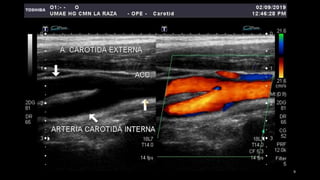

• 3. Identificación y

caracterización adecuada de

las arterias carótida externa

y de la carótida interna.

Carótida externa Carótida interna

Presenta ramificaciones.

Posición anterior.

Características de su curva.

• Patrón de alta resistencia con

relativamente poco flujo de diastólico.

• Aparece más pulsátil con el Doppler

color.

• La muesca dicrota a es más prominente

Pulsación temporal positiva

Otra rama de la bifurcación con bulbo en

su origen.

Posición posterior y trayecto angulado en

sentido posterior.

Onda menos pulsátil en el Doppler color

con flujo diastólico relativamente alto.